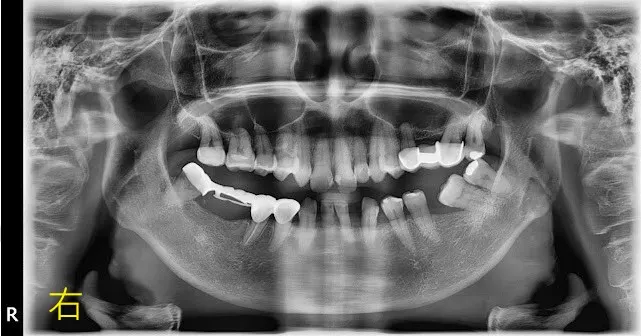

假牙材質4臨床案例---上門牙車禍+雕蠟模型